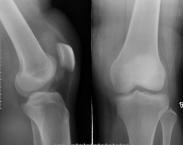

• 脛骨平臺骨折

脛骨平臺骨折(fracture of tibial plateau)是膝關節創傷中最常見的骨折之一。膝關節遭受內/外翻暴力的撞擊,或墜落造成的壓縮暴力等均可導致脛骨髁骨折。由于脛骨平臺骨折...

• 脛骨髁骨折

脛骨髁骨折,約占全身骨折中的0.38%。是較為常見的骨折。好發于青壯年。男性患者多于女性。脛骨髁骨折又較內髁骨折多見。脛骨髁骨折為關節內骨折,骨折波及脛骨近端關節面...